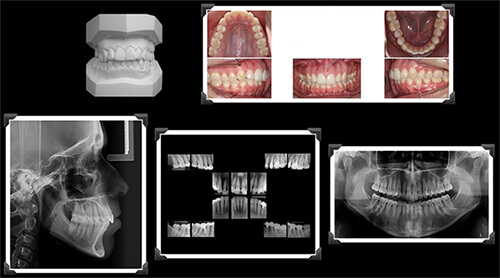

Importância da documentação ortodôntica

🔹 Resposta Objetiva

É indispensável para segurança biológica e planejamento preciso.

🔬 Resposta Aprofundada

Adultos podem apresentar perda óssea, reabsorções radiculares ou alterações articulares.

Portanto, são necessários:

• Radiografia panorâmica

• Telerradiografia

• Análise cefalométrica

• Fotografias

• Escaneamento intraoral

Sem diagnóstico completo, o planejamento torna-se empírico.

12. A documentação ortodôntica é indispensável antes de iniciar o Invisalign?

Sim. A documentação ortodôntica completa é indispensável para diagnóstico preciso e planejamento seguro com Invisalign.

Radiografias, fotografias, escaneamento digital e, quando indicado, tomografia são fundamentais para prever limites biológicos e estruturar a mecânica adequada.

O tratamento com Invisalign baseia-se em planejamento digital tridimensional. Entretanto, a previsibilidade da simulação depende diretamente da qualidade do diagnóstico inicial. A documentação ortodôntica — composta por radiografias panorâmica e cefalométrica, fotografias intra e extraorais, escaneamento digital e análise funcional — fornece base científica para determinar a natureza da maloclusão.

Além da avaliação dentária, é essencial analisar padrões esqueléticos, inclinações incisivas, espessura da tábua óssea alveolar e posição condilar. Movimentos ortodônticos planejados digitalmente podem ultrapassar limites biológicos se não houver avaliação prévia adequada. Portanto, a documentação protege o paciente contra riscos periodontais e instabilidades futuras.

Nos casos adultos, a análise periodontal é ainda mais crítica. A presença de recessões, perda óssea ou biotipo gengival fino exige ajustes na magnitude e direção das forças. A tomografia computadorizada de feixe cônico, quando indicada, amplia a precisão na avaliação tridimensional do suporte ósseo.

Assim, a documentação ortodôntica não representa mera formalidade diagnóstica, mas sim instrumento estratégico que fundamenta todo o planejamento biomecânico. Sem ela, o tratamento perde previsibilidade e segurança biológica.